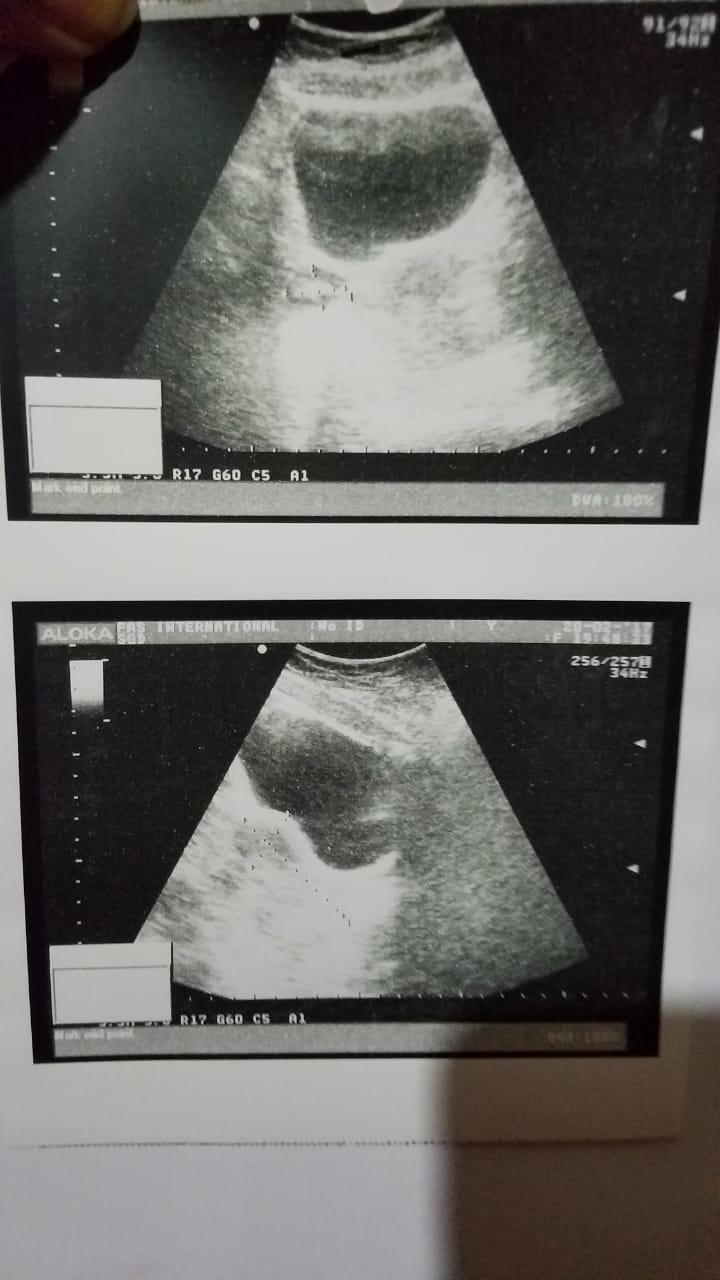

My sister (unmarried) have a hormonal issue, last week she ended her period now after a week again she got periods again with severe pain. she also has a constipation issue. we have got chek up from dr. reports attached. please check and guide what she be done next, what test or medication required?

Her prolactin level is high. She needs Medical treatment for that. And further tests also. Other tests are pelvic ultrasound, serum FSH, LH, thyroid function tests. Testosterone level.

further she needs to hv detailed pelvic ultrasound commenting on ovarian volume,no of follicles in each ovary,CET etc-she needs to hv her hormonal profile done rigjt from her day 2 LH AND ,prolactin,testosterone,thyroid profile,CP an OBG u understand the limitations of online consultations...